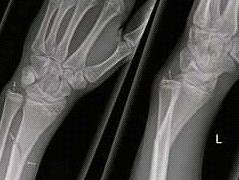

Jaarlijks melden zich bij de huisartsenpost en de Spoedeisende Hulp duizenden mensen met klachten van het bewegingsapparaat. Deze worden vaak veroorzaakt door een trauma. De oudere patiënt die valt, de sporter die een trap heeft gehad van een tegenstander. In dit artikel wordt onder andere aandacht besteed aan de anatomie van het botweefsel, soorten fracturen, symptomen van fracturen en de behandeling.

• bent u op de hoogte hoe een polsfractuur behandeld kan worden